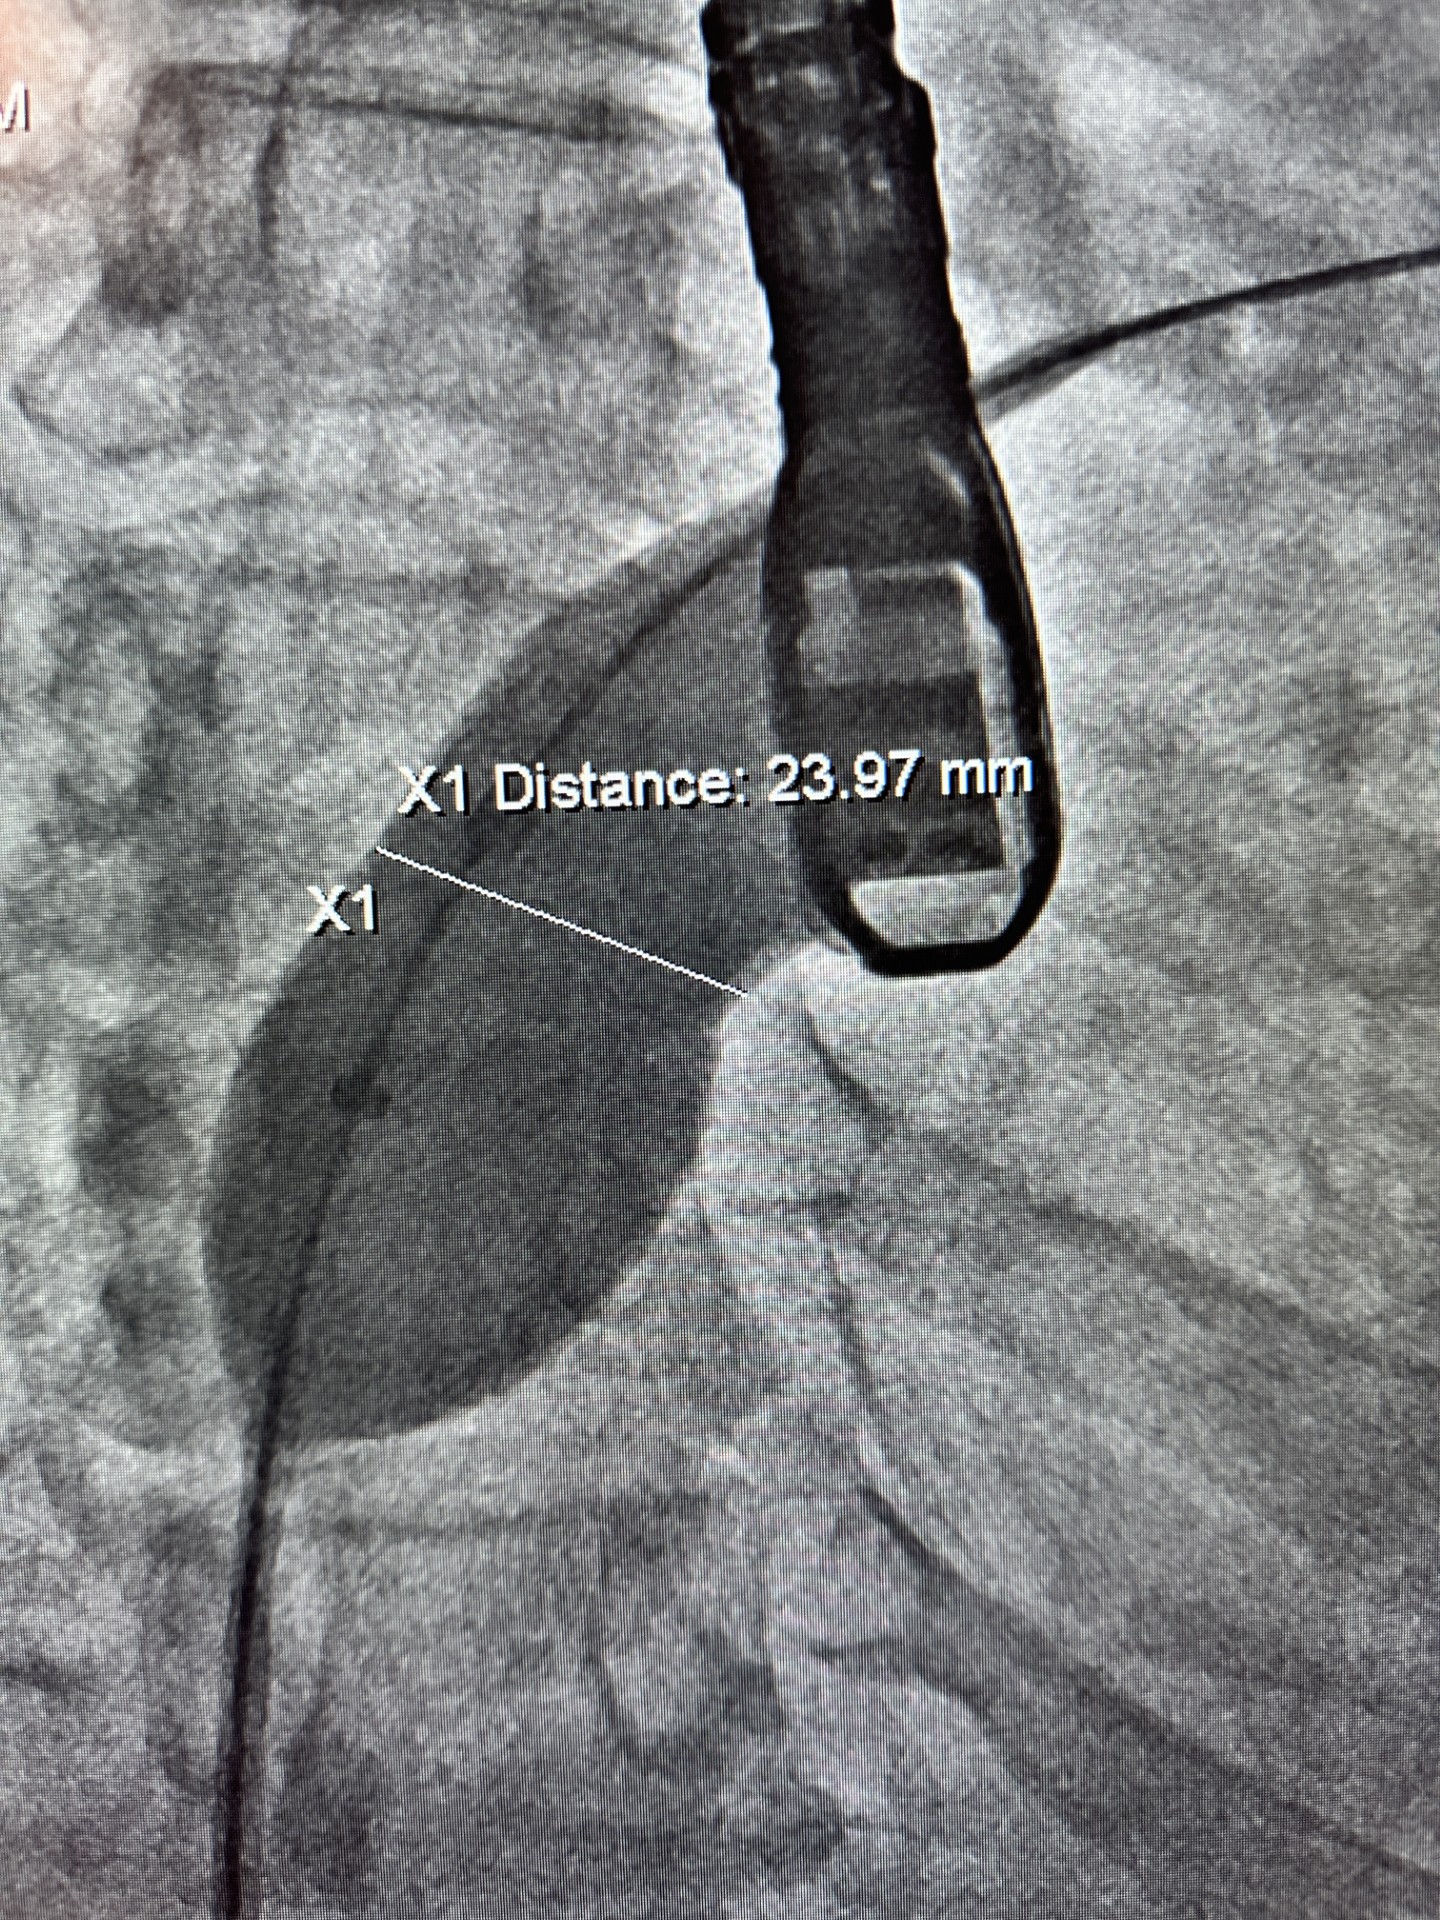

Measurement

- Calibrate cine image between 2 black dots in the sizing balloon (15cm).

- measure with the tool the space between the balloon

- Measurements taken on x-ray image